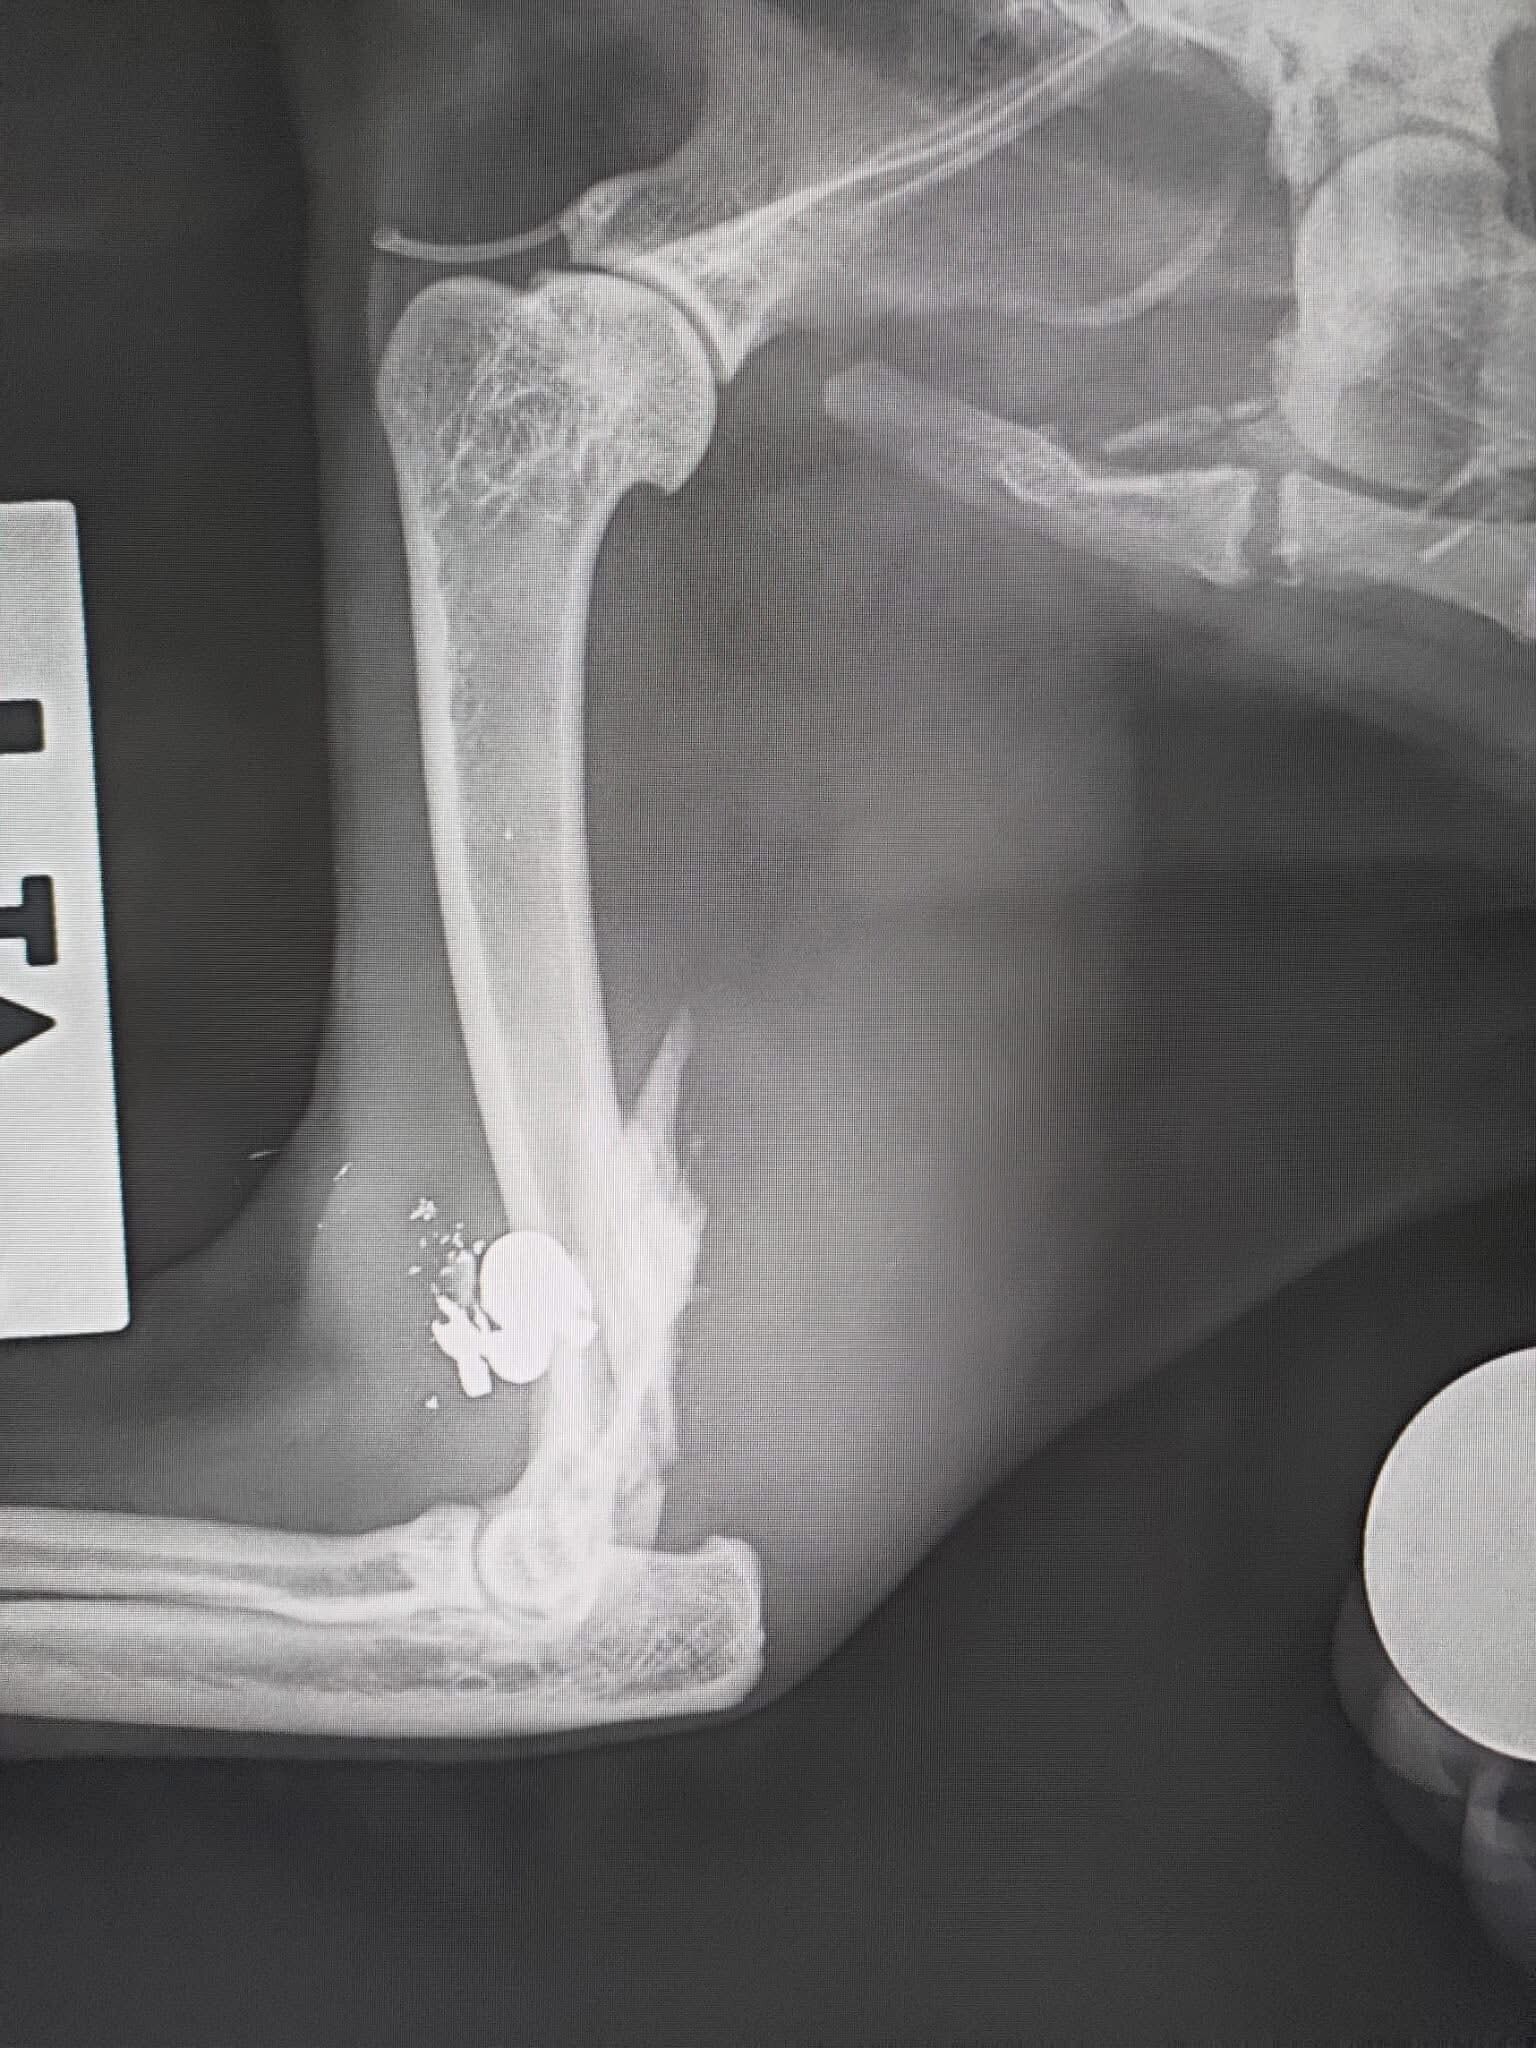

Una delle due ha una zampa gravemente compromessa spiega l'associazione che ha subito avvertito due veterinari della zona che si sono messi immediatamente al lavoro, gli hanno già somministrato le medicine per alleviare il loro dolore. "Stanno cercando una protesi speciale che permetta alle gattine di tornare a vivere alla normalità". "La situazione di una gatta è più critica: oltre alla zampa seriamente danneggiata presenta numerosi pallini di piombo nel corpo. I veterinari stanno valutando con grande attenzione come intervenire per salvarle la vita".